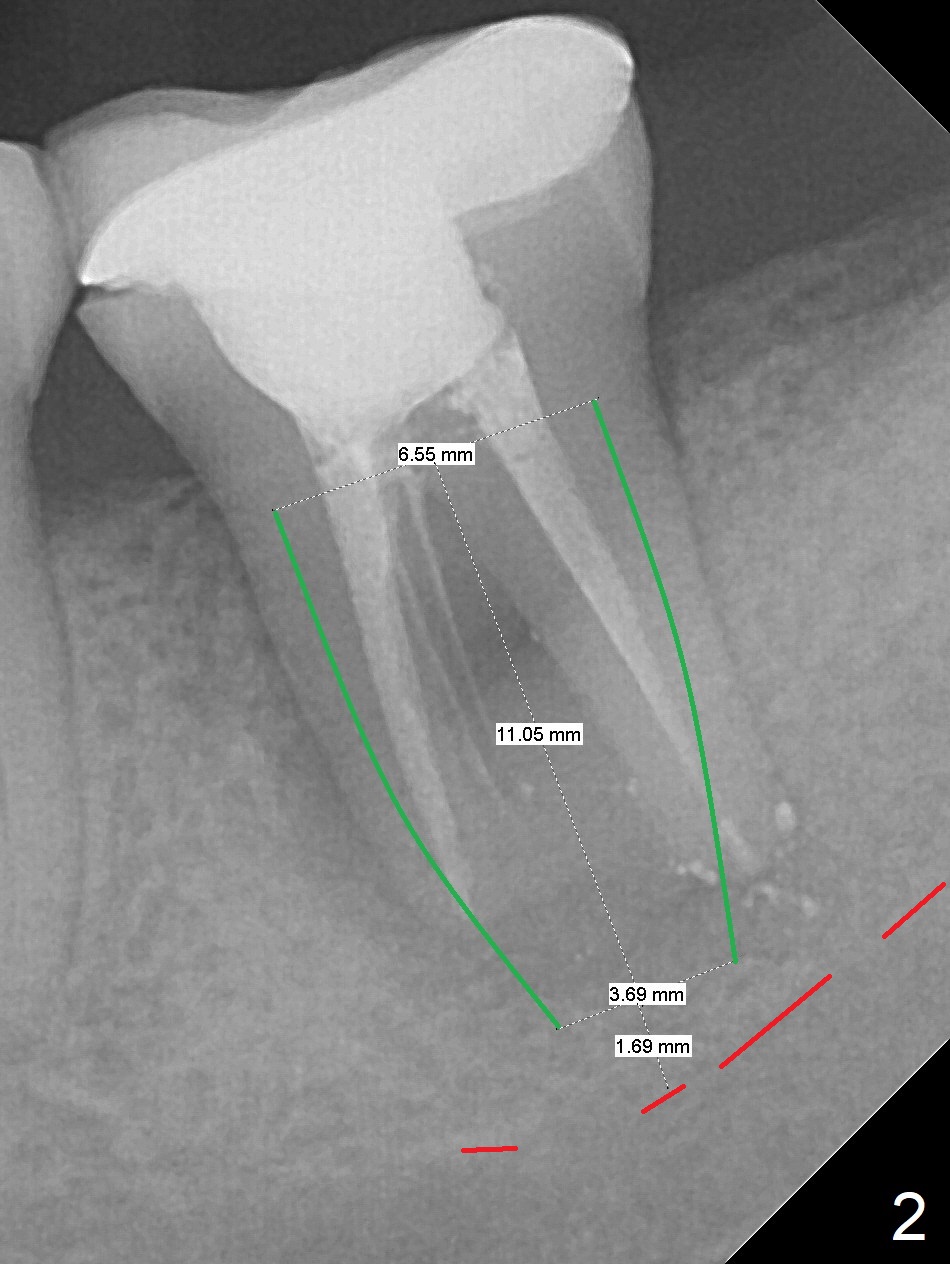

Six months post cementation of #30 implant crown, the 40-year-old woman (CY) returns with chief complaint of lower left abscess.  The buccal furca at #18 has inflamed tissue with large radiolucency (Fig.1 *).  To avoid the Inferior Alveolar Canal (Fig.2 red dashed line), use taps (most likely starting with 5 mm one) and dummy implants to form osteotomy after extraction and granulation tissue removal.  The definitive implant is expected to be 6.5x11 mm.  Switch to Tatum implants if the largest IBS is unable to achieve primary stability.